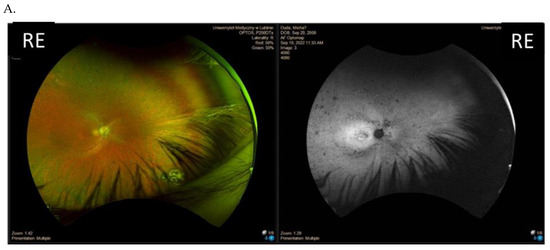

| I (family 1) | c.2442_2445del | 10 | 31 | 0.7 0.7 | Advanced constriction, only V4e remarkable | 277 264 |

| II (family 2) | c.2340_2341del | 12 | 42 | 0.01 0.01 | Advanced constriction, only V4e remarkable | 208 205 |

| III (family 3) | c.2587G>T | 8 | 36 | 0.5 0.6 | Middle constriction, V4e, III4e and I4e remarkable | 143 147 |

| IV (family 4) | c.2389dup | 10 | 22 | 0.7 0.7 | Middle constriction, V4e, III4e remarkable | 223 225 |

| V (family 4) | c.2389dup | 10 | 22 | 0.4 0.2 | Middle constriction, V4e, III4e and I4e remarkable | 260 240 |

| VI (family 5) | c.2455dup | 14 | 25 | 0.6 0.3 | Middle constriction, V4e, remarkable | 205 186 |

| VII (family 6) | c.593G>T | 12 | 20 | 0.5 0.5 | Middle con-striction, V4e, III4e and I4e remarkable | 250 245 |

| VIII (family 7) | c.799G>C | 6 | 47 | 0.2 0.3 | Middle con-striction, V4e, III4e and I4e remarkable | 240 230 |